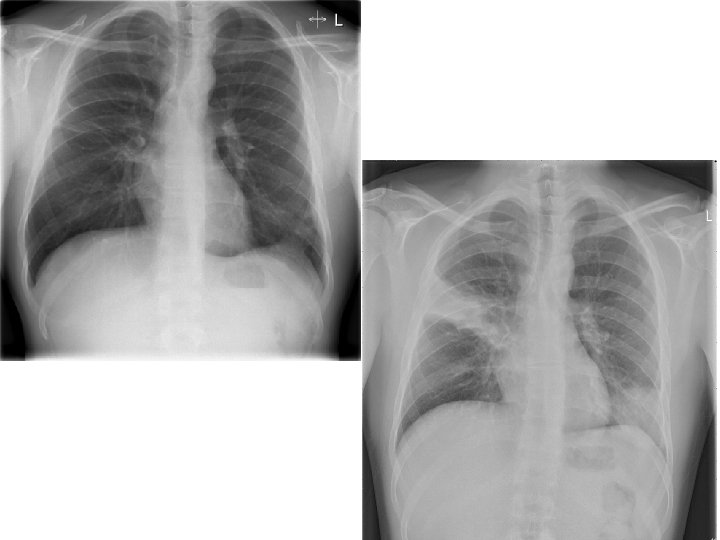

DEFINITION An acute infection of the pulmonary parenchyma that is associated with at least some symptoms of acute infection, accompanied by the presence of an acute infiltrate on a chest radiograph, or auscultatory findings consistent with pneumonia

CLINICAL DIAGNOSIS: CXR Demonstrable infiltrate by CXR or other imaging technique Establish Dx and presence of complications (pleural effusion, multilobar disease) May not be possible in some outpatient settings CXR: classically thought of as the gold standard

PATTERN AND POSSIBLE DIAGNOSIS Lobar: S. pneumo, Kleb, H. flu, GN Patchy: Atypicals, viral, Legionella Interstitial: Viral, PCP, Legionella Cavitary: Anaerobes, Kleb, TB, S. aureus, fungi Large effusion: Staph, anaerobes, Kleb